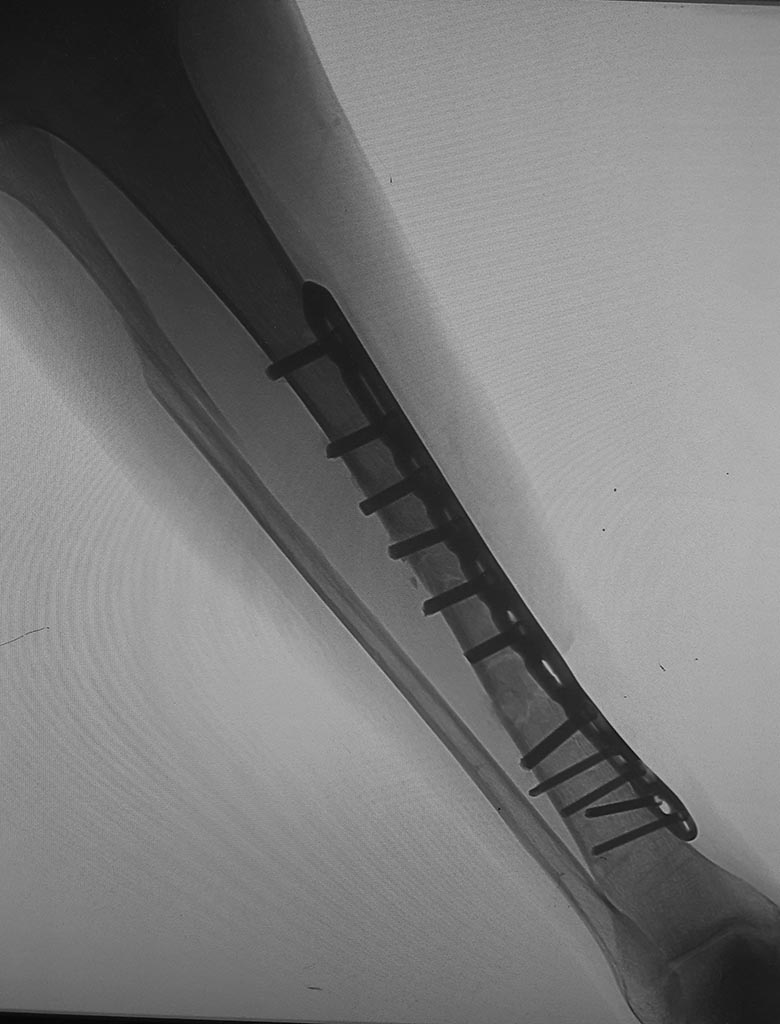

[Ortho] Дефект м.тк. на голени после мос

Спасибо. 1 месяц с момента операции. Последние посевы (2) из раны -

роста нет. Больше склоняюсь к удалению пластины,  БИОС и последующему

местному лечению. Возможность VAC - только изготовить самостоятельно из

ваакуума ( так думаю, есть опыт ожидания). Картинка через месяц с

момента операции (06.03.20). По поводу разного рода пластик раны было